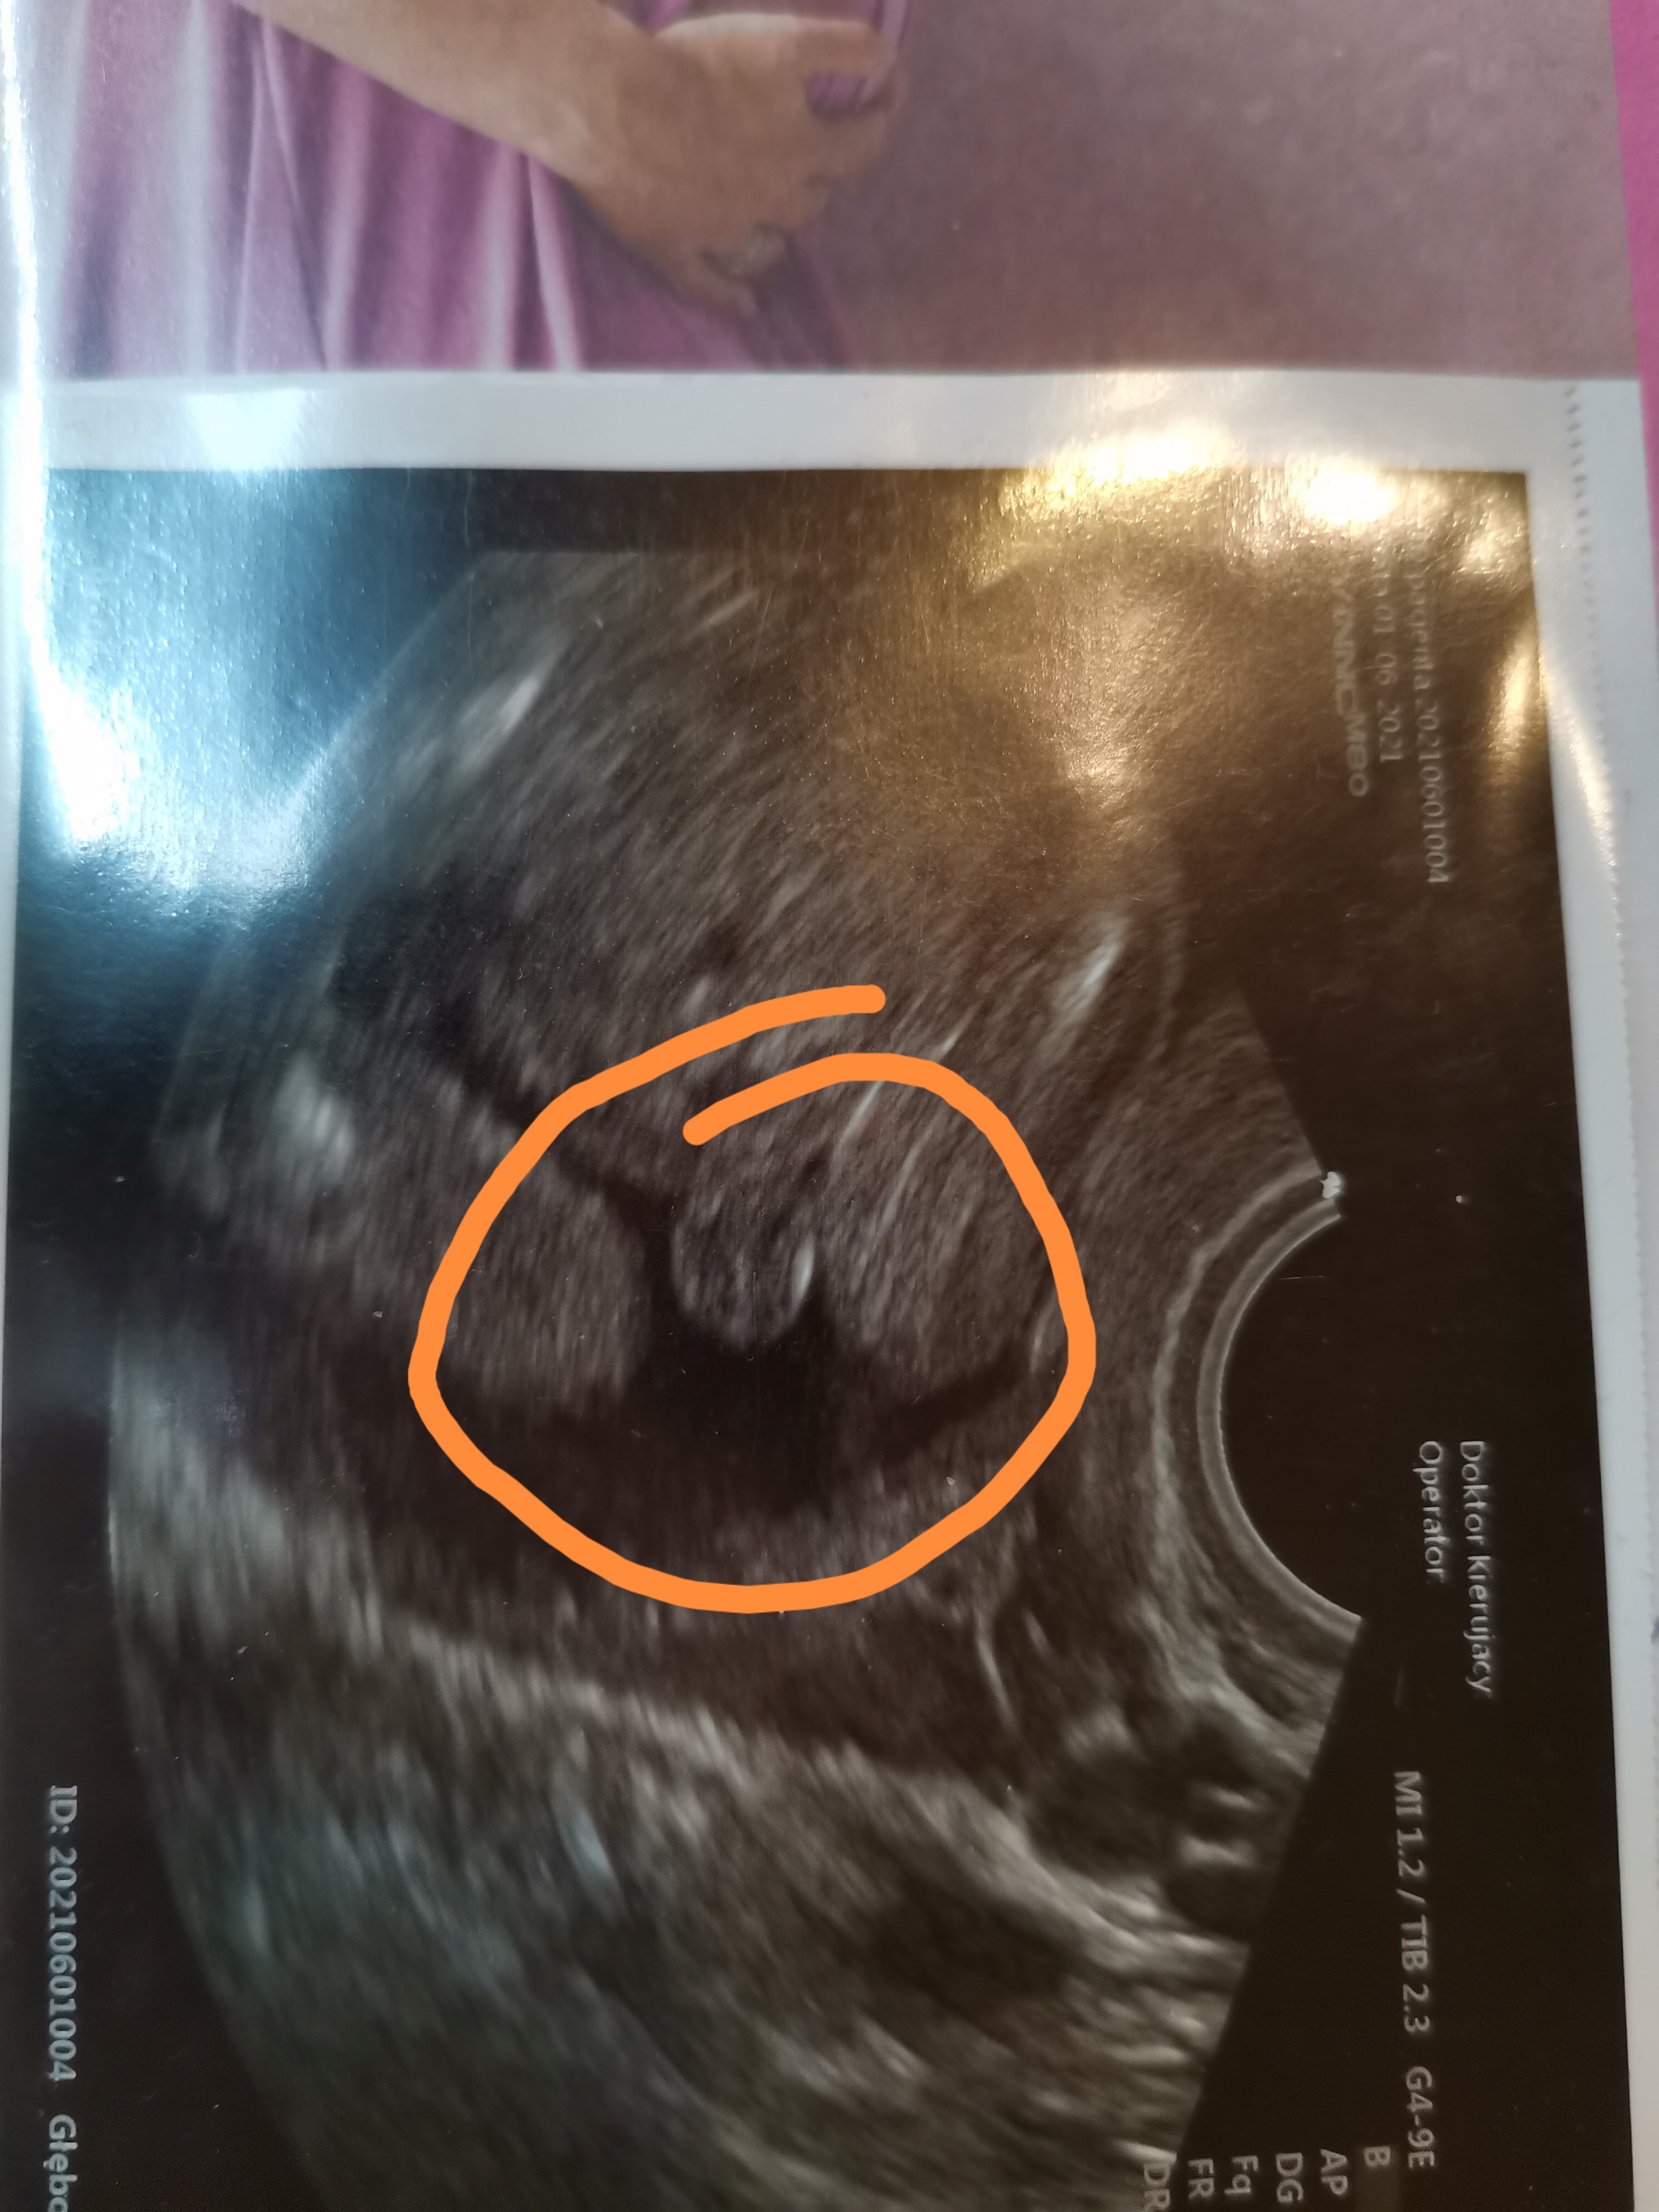

Cześć, mam pytanie. Dwóch lekarzy powiedziało mi, że będę mieć córeczkę, aczkolwiek mam wątpliwości. Po przybliżeniu zdjęcia coś tam zauważyłam :) Jak myślicie? Mogę mieć jakieś obawy, czy raczej sobie wymyślam?

Podobno jak są tam dwie kreseczki to dziewczynka, moim zdaniem są dwie kreseczki.